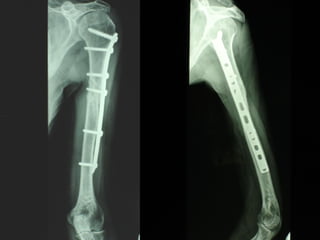

Dal Gennaio 2000 al Febbraio 2006 abbiamo trattato 167 fratture chiuse  con placca percutanea  in 164 pazienti :  27 lesioni diafisarie di gamba, 12 piloni tibiali ,  11 fratture prossimali di tibia, 36 fratture sovracondiloidee di femore, 17 fratture diafisarie di femore, 43 fratture metaepifisarie prossimali di omero, 21 diafisarie d’omero.  156 guarigioni 8 fallimenti

Dal Giugno 2002 al Dicembre 2004 abbiamo trattato 5 fratture esposte: 3 di tibia e 2 di ulna 5 guarigioni

I buoni risultati ottenuti dipendono da 5 punti fondamentali:   una accurata riduzione percutanea della frattura  precise vie di accesso  l’utilizzo della placca che consenta il più lungo braccio di leva possibile il pretensionamento della placca  una sintesi con un ridotto numero di viti

Precise vie di accesso

Placche lunghe e pretensionate

Placche lunghe e pretensionate Sintesi con un ridotto numero di viti